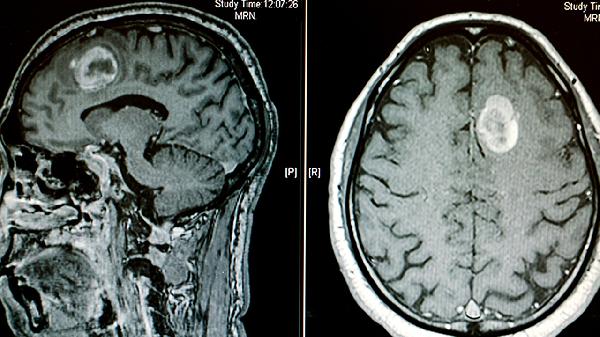

脑肿瘤患者可能会出现流鼻血,但并非典型症状。脑肿瘤的症状主要有头痛、恶心呕吐、视力障碍、肢体无力、癫痫发作等。流鼻血更常见于鼻腔局部病变或血液系统疾病。

头痛是脑肿瘤最常见的症状,通常表现为持续性钝痛或胀痛,晨起时加重,咳嗽或低头时疼痛加剧。恶心呕吐多伴随头痛出现,呈喷射性呕吐,与进食无关。视力障碍包括视物模糊、视野缺损或复视,可能与肿瘤压迫视神经或视交叉有关。肢体无力常表现为单侧肢体活动不灵活,严重时可出现偏瘫。癫痫发作形式多样,包括全身强直阵挛发作或局部抽搐,与肿瘤刺激大脑皮层有关。

脑肿瘤患者应保持规律作息,避免剧烈运动和情绪激动。饮食宜清淡易消化,适当补充优质蛋白和维生素。出现不明原因头痛、呕吐或神经系统症状时,应及时进行头颅CT或MRI检查。确诊脑肿瘤后需遵医嘱治疗,可选择手术切除、放疗或化疗等方案。日常注意观察症状变化,定期复查评估病情进展。